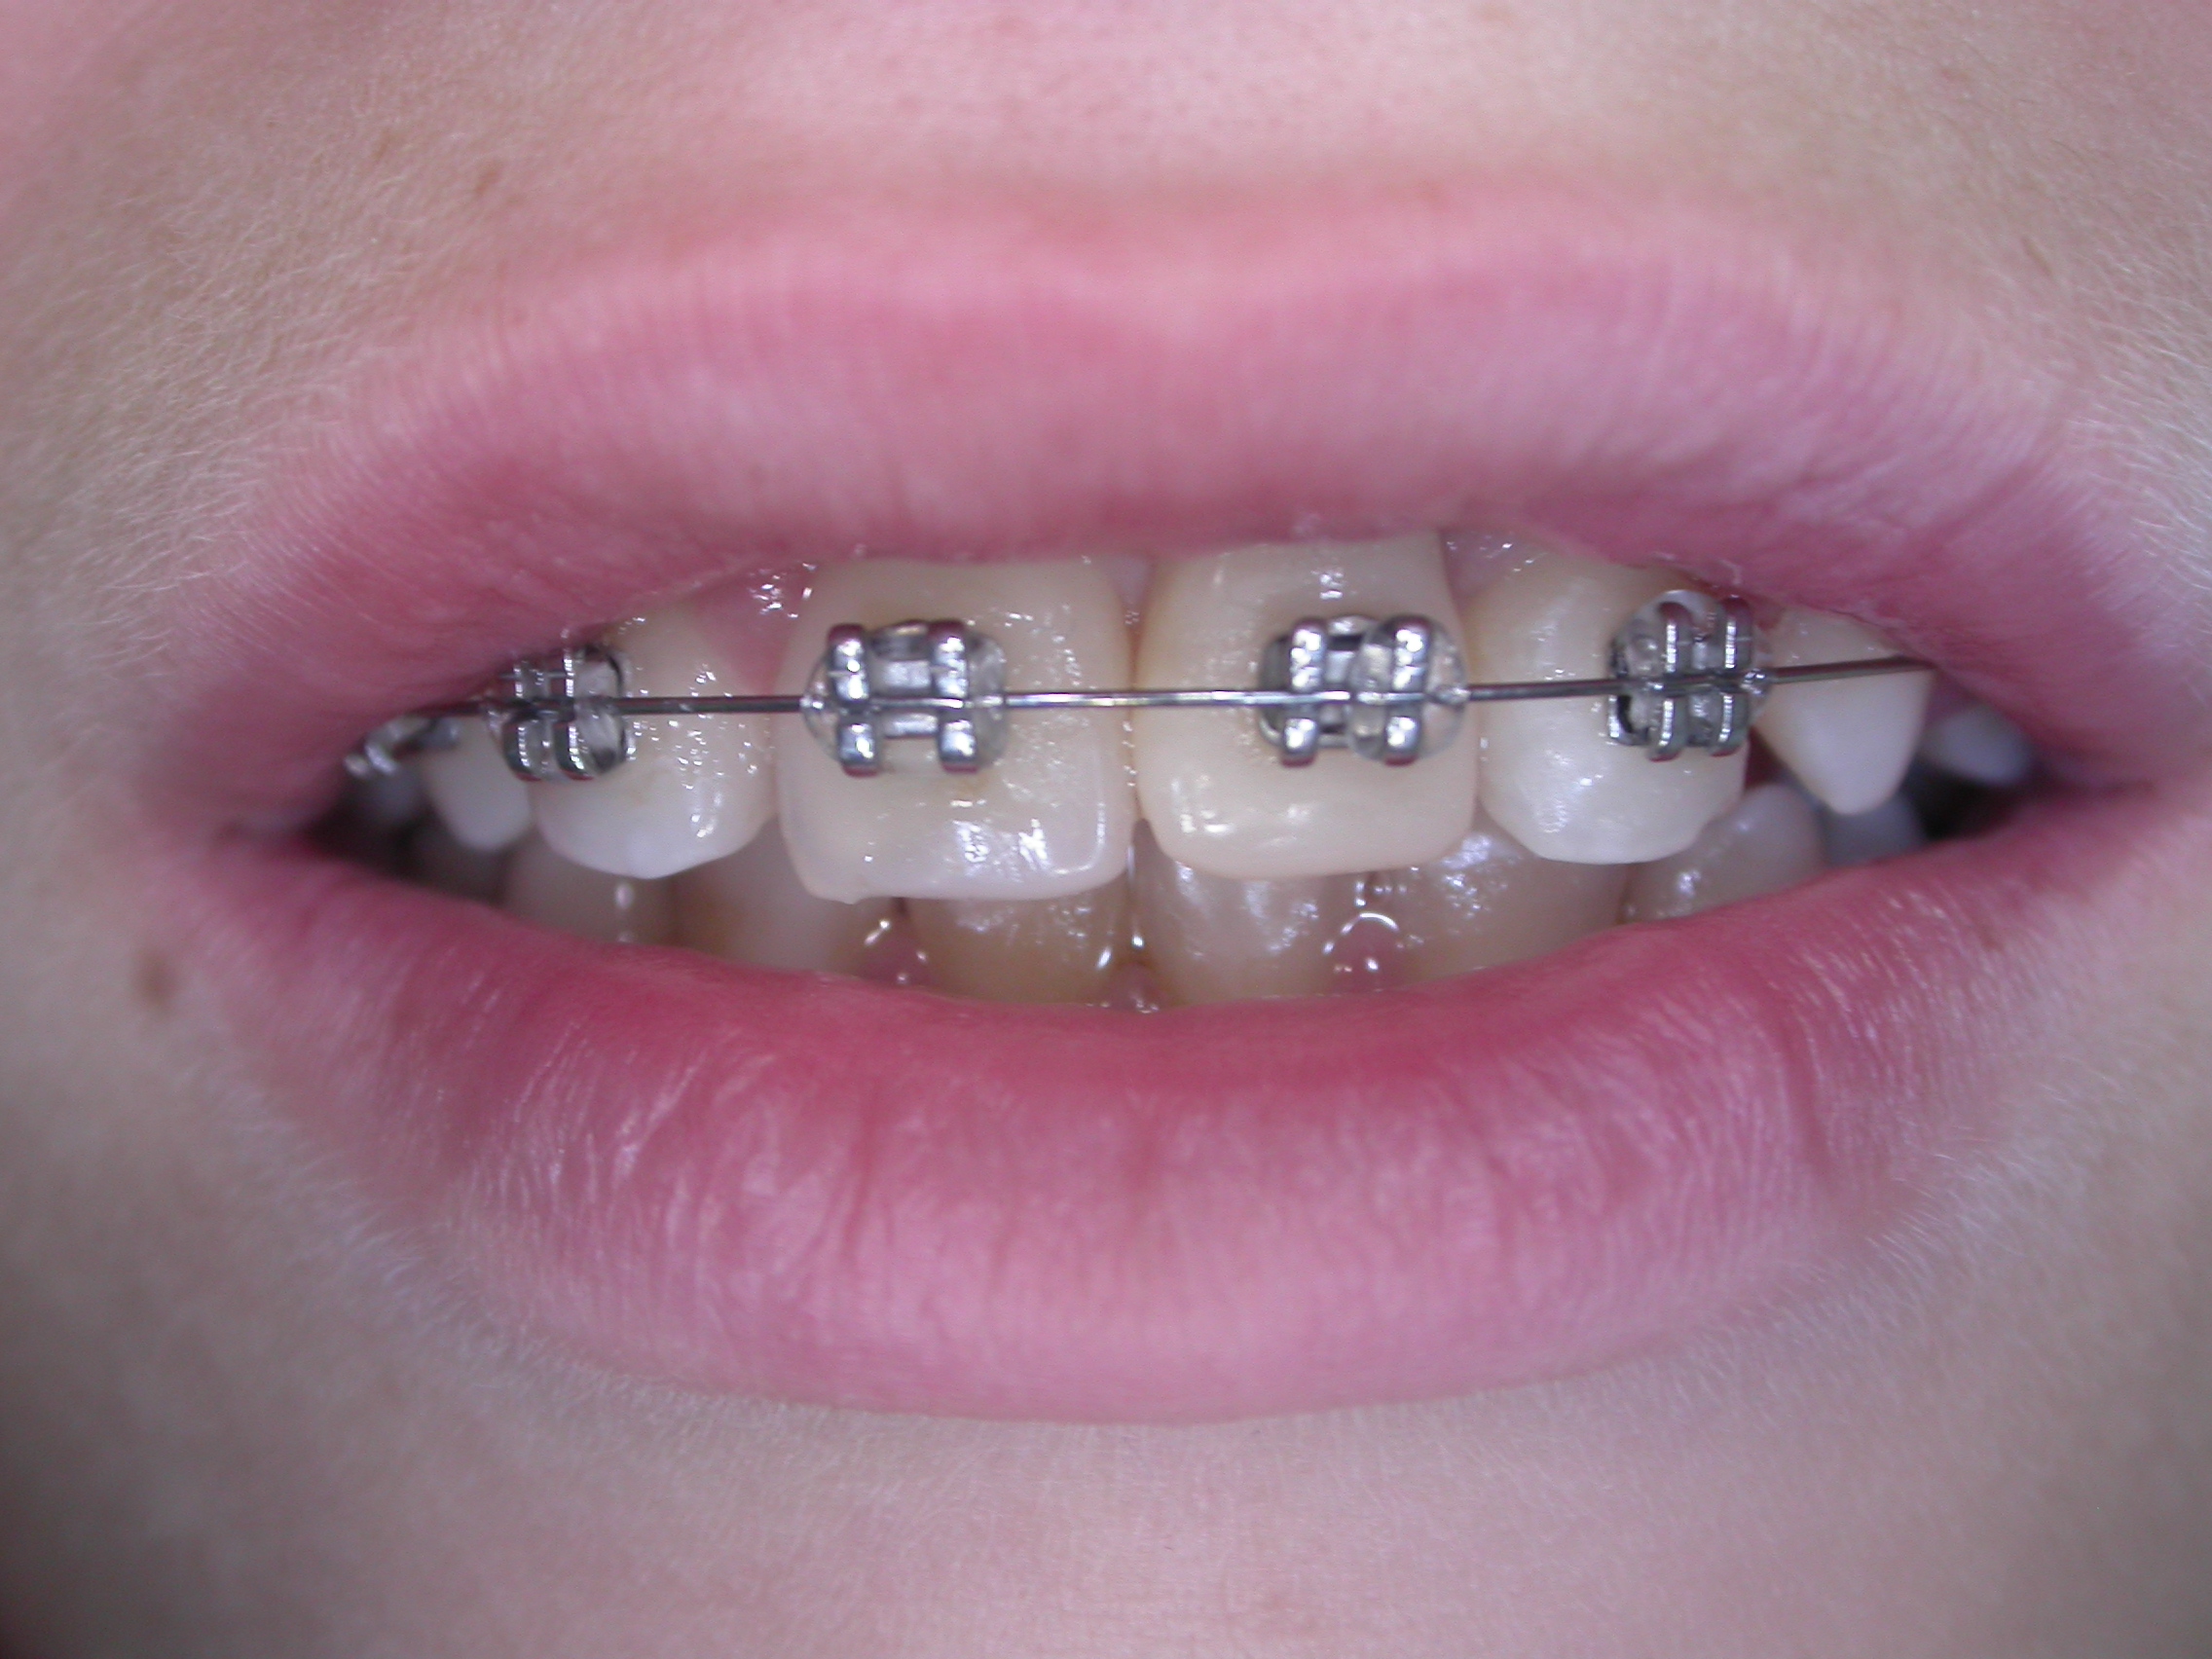

Nel caso qui visualizzato, invece, è stato realizzato un mantenitore per preservare lo spazio dopo avulsione traumatica dell'incisivo.

Il piccolo paziente per questa mancanza e per la malocclusione che lo affligge si presenta alla nostra osservazione. Dopo una prima fase di allineamento e di recupero dello spazio fisiologico per un futuro riposizionamento del dente, viene applicato all'apparecchio ortodontico fisso un dente modellato in resina per il recupero e il mantenimento dello spazio. Il bordo incisale del dente in resina, inizialmente allineato con i contigui, adesso risulta leggermente più apicale per movimenti degli stessi.